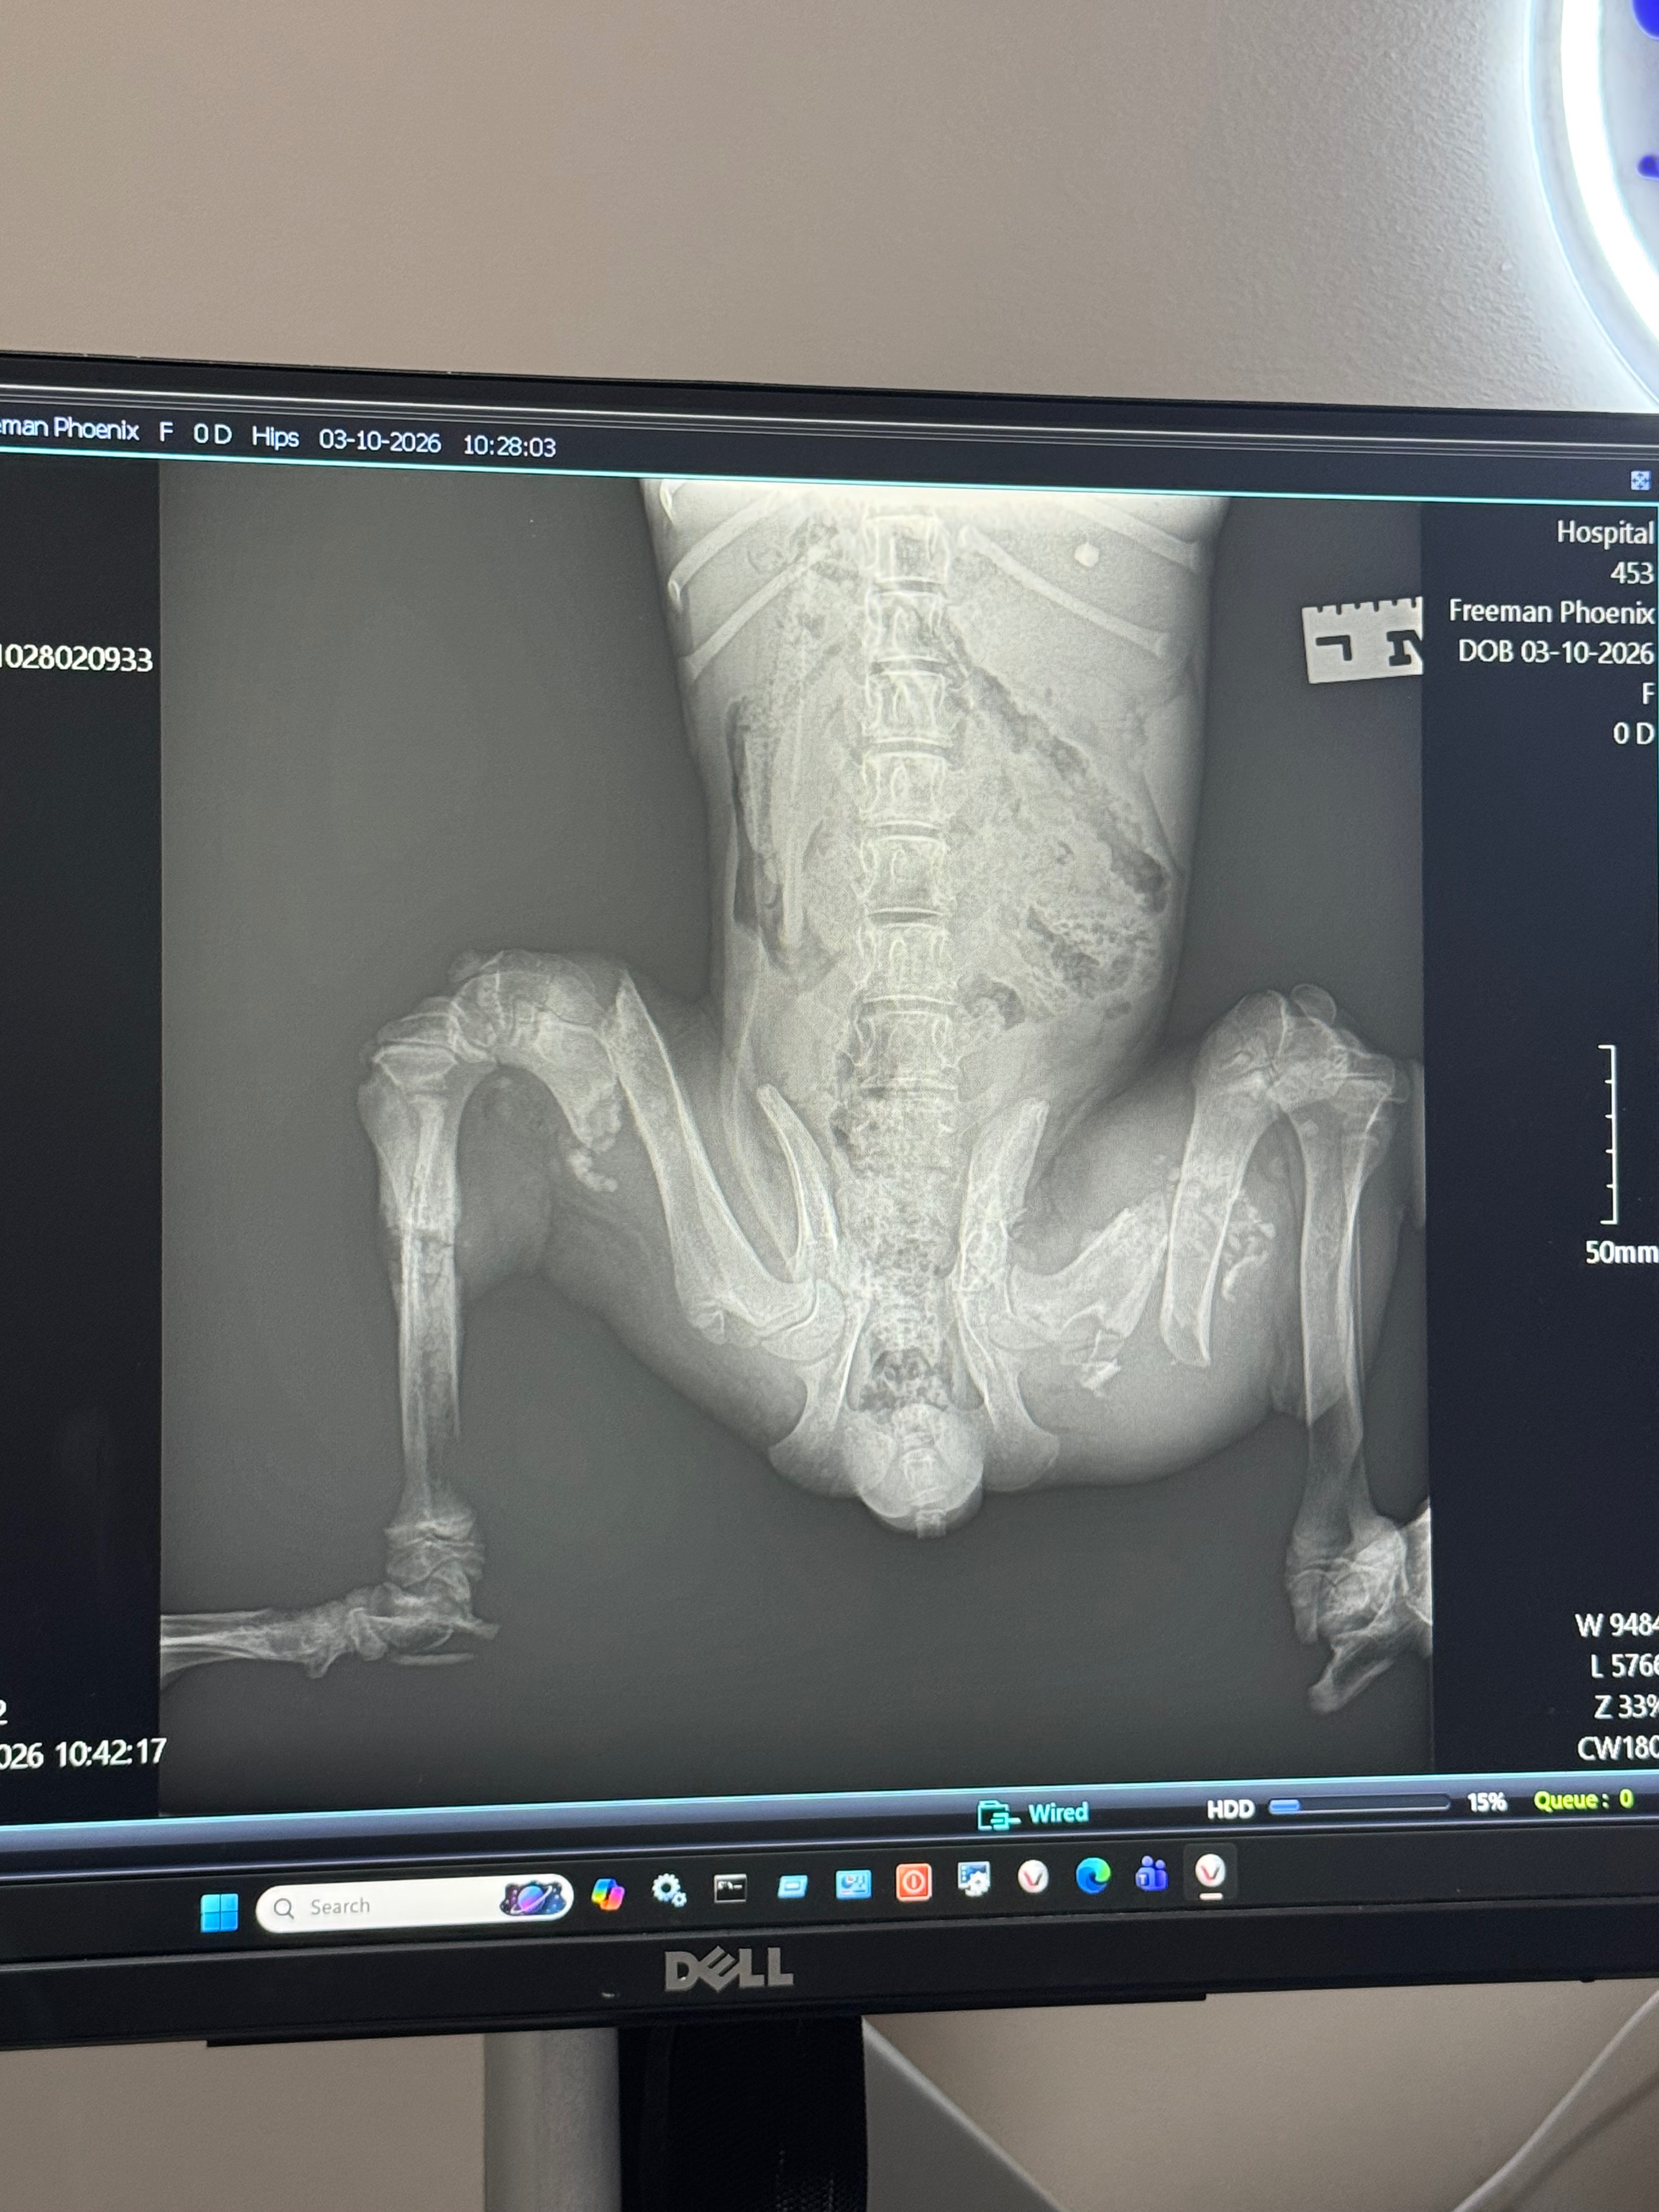

Phoenix was found dumped and severely injured. Assuming she was hit by a vehicle. We went to the vet today to get X-rays! She’s making such great progress! Her injuries are guesstimated 3+ weeks when it happened. Unfortunately she does require surgery. She has a right tibial fracture (which has already healed) she has a right femur fracture and a left femur fracture. The surgery required will possibly be plates in both femurs. One has already started to fuse back together. She’s a fighter. She’s so young she deserves her happy ever after! But surgery will be expensive. It’s a very hard decision but I would like to save her if possible!! Time is of the essence though because once the worst side heals they might not be able to operate on her! Magnolia Veternarian Surgery in Tupelo,MS looked over the xrays and said to fix both sides would be $3600-$4400 even the smallest donations adds up! Receipts can be given for proof. This vet is not set up to take donations over the phone like this (per the lady in the office!) please help me give her a second chance at life!